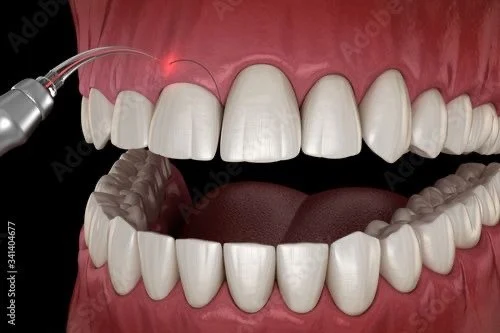

Beljenje zuba

1. Kućno beljenje

Obavlja se izradom individualnih splintova za svakog pacijenta i aplikovanjem gela.

Rezultati su uocljivi nakon nekoliko dana.

2. Ordinacijsko beljenje

Ovaj vid beljenja obavlja se u stomatološkoj stolici, u skladu sa indikacijom i preporukom od strane terapeuta. Za manje od jednog sata izlazite sa blistavim osmehom.

3. Beljenje devitalizovanih(mrtvih) zuba

Nakon endodontske terapije ili usled traume zub vremenom tamni, usled čega se opredeljujemo za ovaj vid pojedinačnog beljenja zuba u ambulantnim uslovima.